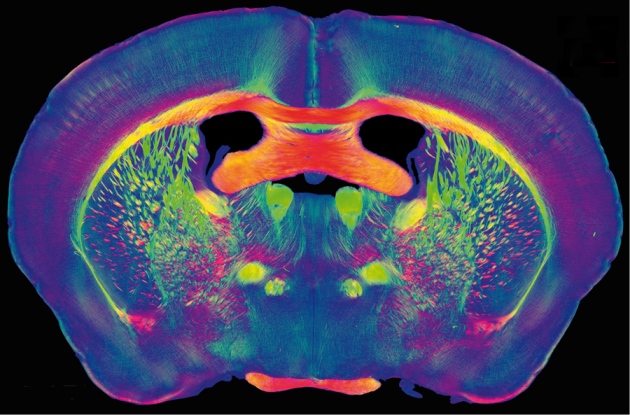

They actually started with the Blue Brain Project (2005), modelizing a rat brain to to create a synthetic brain by reverse-engineering the mammalian brain down to the molecular level.